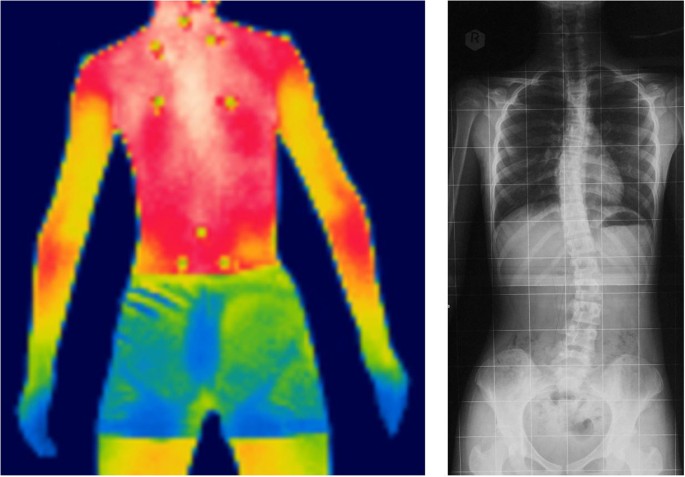

في هذا المقال، نشرح بلغة مبسطة نتائج دراسة حديثة استخدمت تقنية التصوير الحراري بالأشعة تحت الحمراء (Infrared Thermography – IRT) لمتابعة درجة حرارة ظهر مرضى اعوجاج العمود الفقري أثناء ممارسة التمارين الهوائية، ونقدم أهم النصائح العملية للأهل والمرضى لضمان سلامة الأطفال والمراهقين أثناء النشاط البدني.

تقنية التصوير الحراري بالأشعة تحت الحمراء (IRT) هي طريقة غير جراحية لقياس درجة حرارة سطح الجسم بدقة عالية.

هدفت الدراسة إلى معرفة كيف تتغير درجة حرارة ظهر مرضى اعوجاج العمود الفقري مقارنةً بالأشخاص الأصحاء أثناء ممارسة تمارين هوائية مثل ركوب الدراجة لمدة 30 دقيقة.

كما ركزت على معرفة ما إذا كانت العضلات الخلفية، مثل العضلة شبه المنحرفة (Trapezius) وعضلة المربّع القطني (Quadratus Lumborum)، تُظهر تفاوتًا في التدفئة أو تغيّرًا غير متساوٍ بعد التمرين.

قام جميع المشاركين بأداء تمرين ركوب الدراجة الهوائية لمدة 30 دقيقة، بينما تم قياس درجة حرارة ظهرهم باستخدام IRT.

بالإضافة لذلك، تم تحليل قيم النشاط الكهربائي للعضلات الخلفية بعد التمرين باستخدام قياس EMG (Electromyography) لتقييم استجابة العضلات.

أظهرت العضلات في ظهرهم، مثل العضلة شبه المنحرفة وعضلة المربّع القطني، تفاوتًا في درجة الحرارة أو ارتفاعًا غير متساوٍ بعد التمرين.

هذا يشير إلى خلل محتمل في توزيع الحرارة أو ضعف قدرة الجسم على تبديد الحرارة بشكل متوازن.